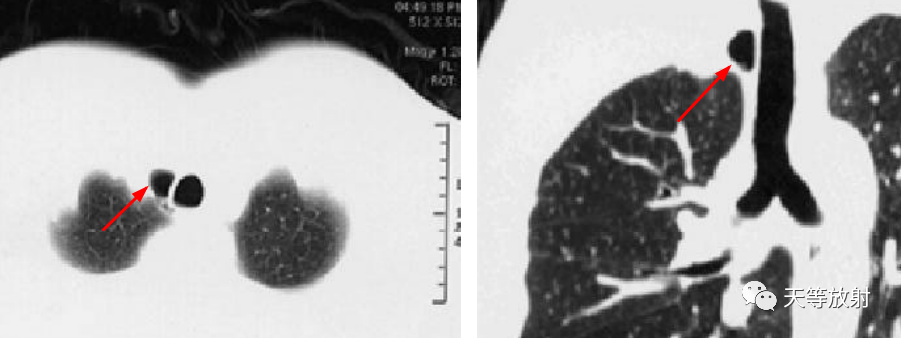

文献病例:气管旁憩室,细线样密度影与气管相连通。

上图:文献病例,气管憩室,内见分隔影。

上图,气管憩室,有一较短细的管道相通,类似小蝌蚪样改变。